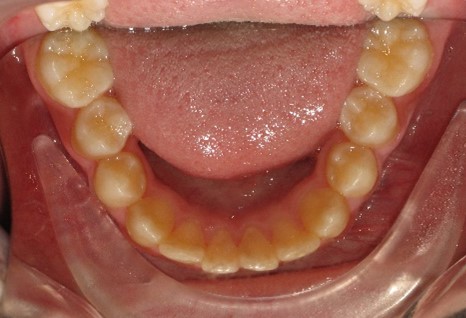

В последующем, после дистализации моляров на верхней челюсти, аппарат снят и на втором этапе ортодонтического лечения фиксирована брекет-система пассивного самолигирования NexStep Pro с пазом 0.22 (стандарт). Уникальная конструкция замка-слайда обеспечивает повышенный контроль торка и ротации, а прецизионность паза брекета дает полную реализацию программы, заложенную в брекетах данной системы SLS. (рис.6 )

После дистализации боковых сегментов на верхней челюсти и правильной постановки клыков в зубной ряд проведена фиксация аппарата на нижний зубной ряд и дальнейшая коррекция окклюзии проводится по стандартному протоколу, т.е. нормализация формы зубных рядов на верхней и нижней челюсти с правильной постановкой зубов по торку в боковых и во фронтальном отделах, что дает реализация программы, заложенная в пассивной самолигирующей брекет- системе NexStep Pro 0.22. (рис.8)

Рис.8. Этап контроля торка на верхней челюсти и фиксация аппарата на нижней челюсти для проведения этапа нивелирования.